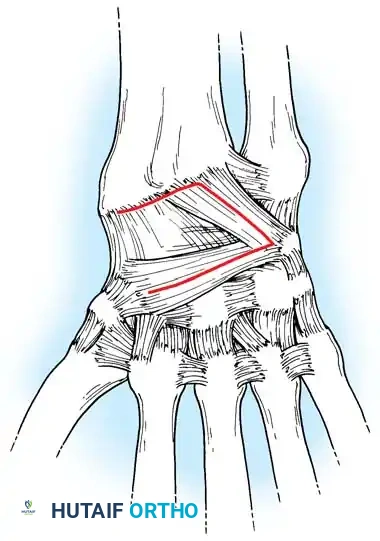

Surgical Management of Scapholunate Dissociation

Acute Injuries (<4 weeks):

Closed reduction with percutaneous pinning (placing 0.045-inch K-wires from the scaphoid to the capitate and lunate) can be attempted. However, open reduction through a dorsal approach is generally preferred. This allows direct closure of the scapholunate gap, K-wire fixation, and primary repair of the dorsal SL interosseous ligament using suture anchors.